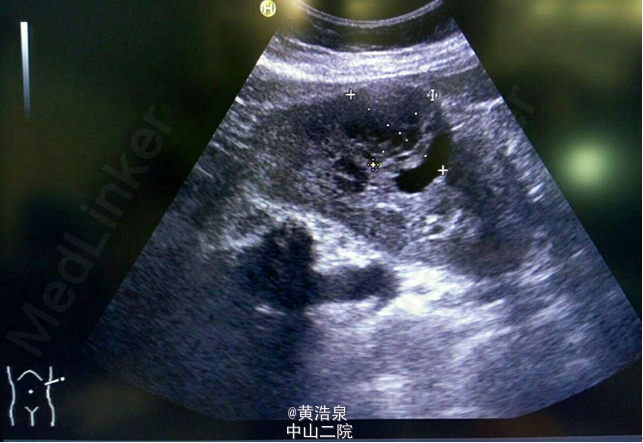

患者女,60岁,51kg,诊断为“左肾肿物”, 否认“高血压、糖尿病”,否认有食物、药物过敏史;实验室检查(尿RT:白细胞270个/ul,红细胞 100个/ul;予未见特殊),胸片、ECG均未见异常,拟在静吸复合全麻下行“腔镜下左肾部分切除术(腹膜后入路)”。

肾脏B超如下图